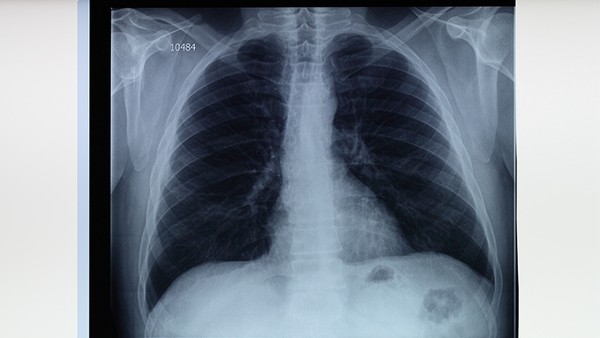

得过肺结核做皮试一般是指感染过肺结核的患者进行PPD皮肤试验。通常情况下,感染过肺结核的患者在经过规范治疗后,PPD皮肤试验结果会转为阴性。

1.已经治愈:如果曾经患有肺结核,并且已经接受正规抗结核药物治疗,在这种情况下,即使进行了PPD皮肤试验,也会出现假阴性的情况,因为此时体内不存在结核杆菌,所以不会产生相应的抗体,也不会导致局部红肿和硬结。这种情况下的PPD皮肤试验结果通常是阴性的。

另外,还有可能是由于陈旧性肺结核所致,需要进一步完善相关检查明确原因并积极处理。

部分患者可能是因为自身免疫力低下,再次受到结核菌侵袭所引起的疾病,从而导致身体内存在结核杆菌,这时就会使体内的结核抗体无法被清除掉,所以在进行PPD皮肤试验时会出现阳性的情况。可以遵医嘱服用盐酸乙胺丁醇片、吡嗪酰胺片等药物来控制病情的发展。